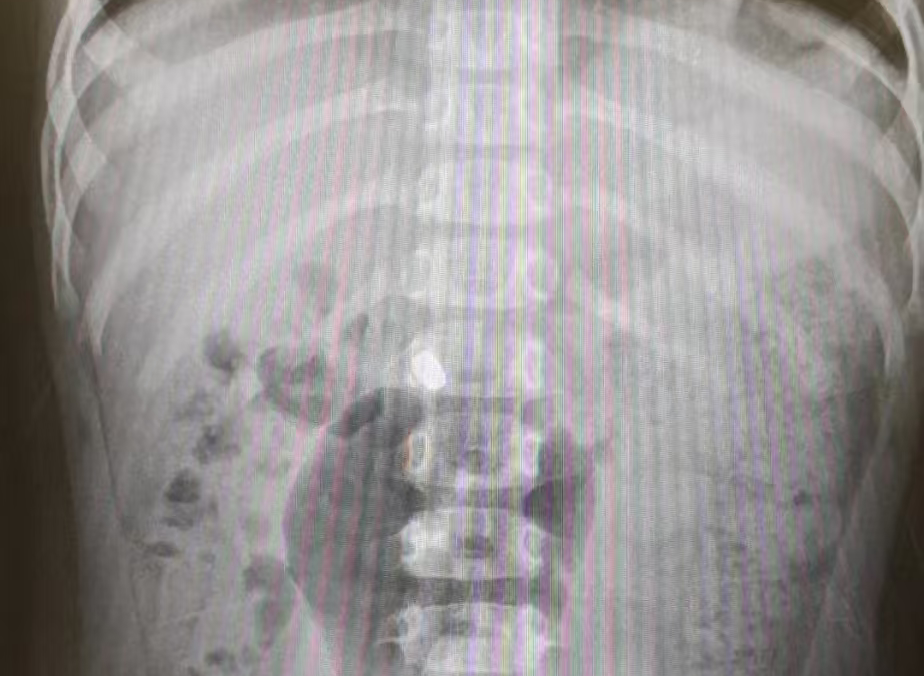

03

电池等腐蚀性异物

一旦 纽扣电池 卡在狭窄的食道,电流加化学性腐蚀,可在短时间内引发消化道巨大创伤。

△纽扣电池(已通过食道段)